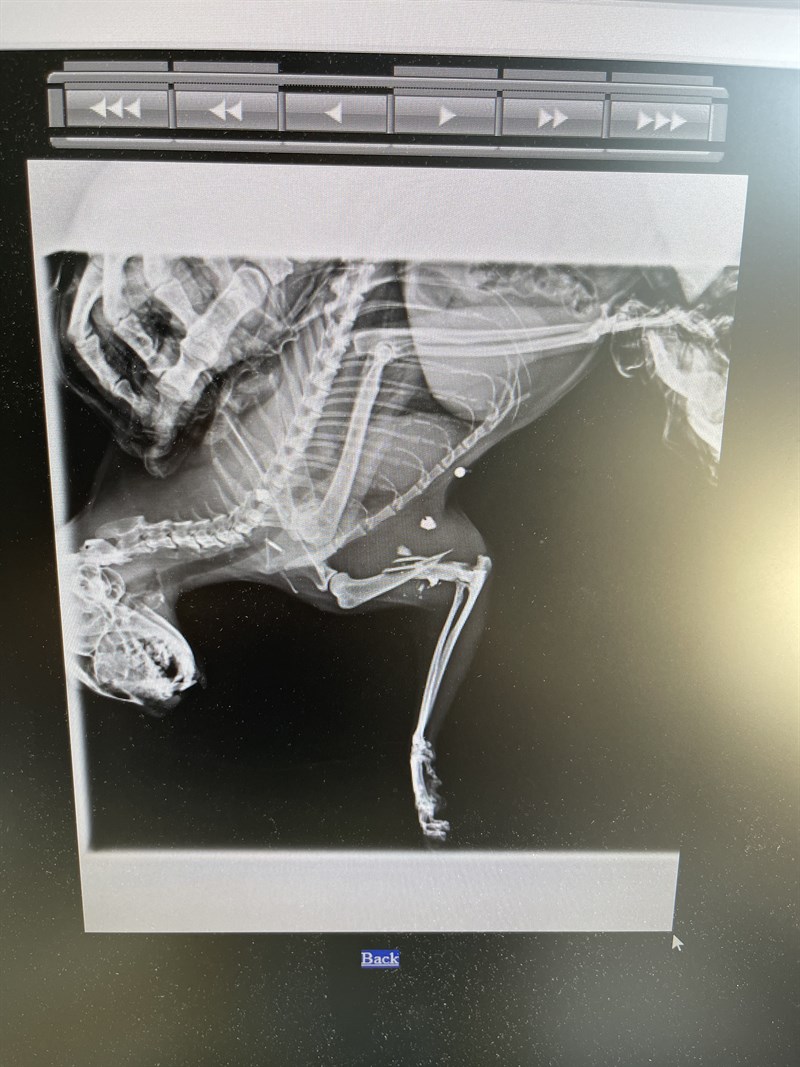

È successo a maggio: hanno sparato a un gatto che da anni vive nella colonia felina della stazione di S. Piero a Sieve. Il gatto si stava allontanando leggermente dalla colonia quando è stato colpito da più pallini, uno dei quali ha fratturato l'osso della sua zampa anteriore, creando una frattura interna.

Le istituzioni competenti sono state immediatamente avvertite tramite posta elettronica e telefonate. La ASL veterinaria di Firenze ha inizialmente negato la possibilità di prendersi cura dell'animale. Tuttavia, qualche giorno dopo, sono stati ricontattati e informati che il gatto doveva essere portato alla clinica veterinaria di S. Piero a Sieve, con cui avevano una convenzione.

Successivamente, la ASL ha contattato l'ambulatorio veterinario in cui il gatto era stato già trasferito, comunicando che non avrebbero coperto le spese per le cure, e che spettavano al Comune. Il Comune, a sua volta, ha risposto che non era di sua competenza intervenire e che non disponeva dei fondi necessari. Nonostante ciò, grazie alla tenacia della referente e delle volontarie, il gatto è stato operato con successo nella clinica veterinaria e, grazie alla collaborazione del titolare dell'ambulatorio, che ha interagito con l'ASL, le spese saranno sostenute dall'azienda stessa.